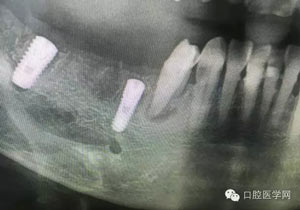

病例1:患者迫切希望保留自己的這一顆牙齒,根尖周陰影比較大,二度松動.而且旁邊有種植修復(fù)體,和患者溝通好后,治療好后觀察一個月后冠修復(fù),因為有種植的后期修復(fù),所以有了機會觀察,術(shù)后三個月和術(shù)后四個月,根尖恢復(fù)的還算不錯,希望能夠繼續(xù)觀察下去.這樣子的病例,做的時候我們一定要非常的小心,和患者要有充分的溝通以及不同科室的溝通然后決定怎么樣做比較好,假如就是出現(xiàn)了問題,到時候我們也比較好處理些,免得我們自己到時候不好收場。